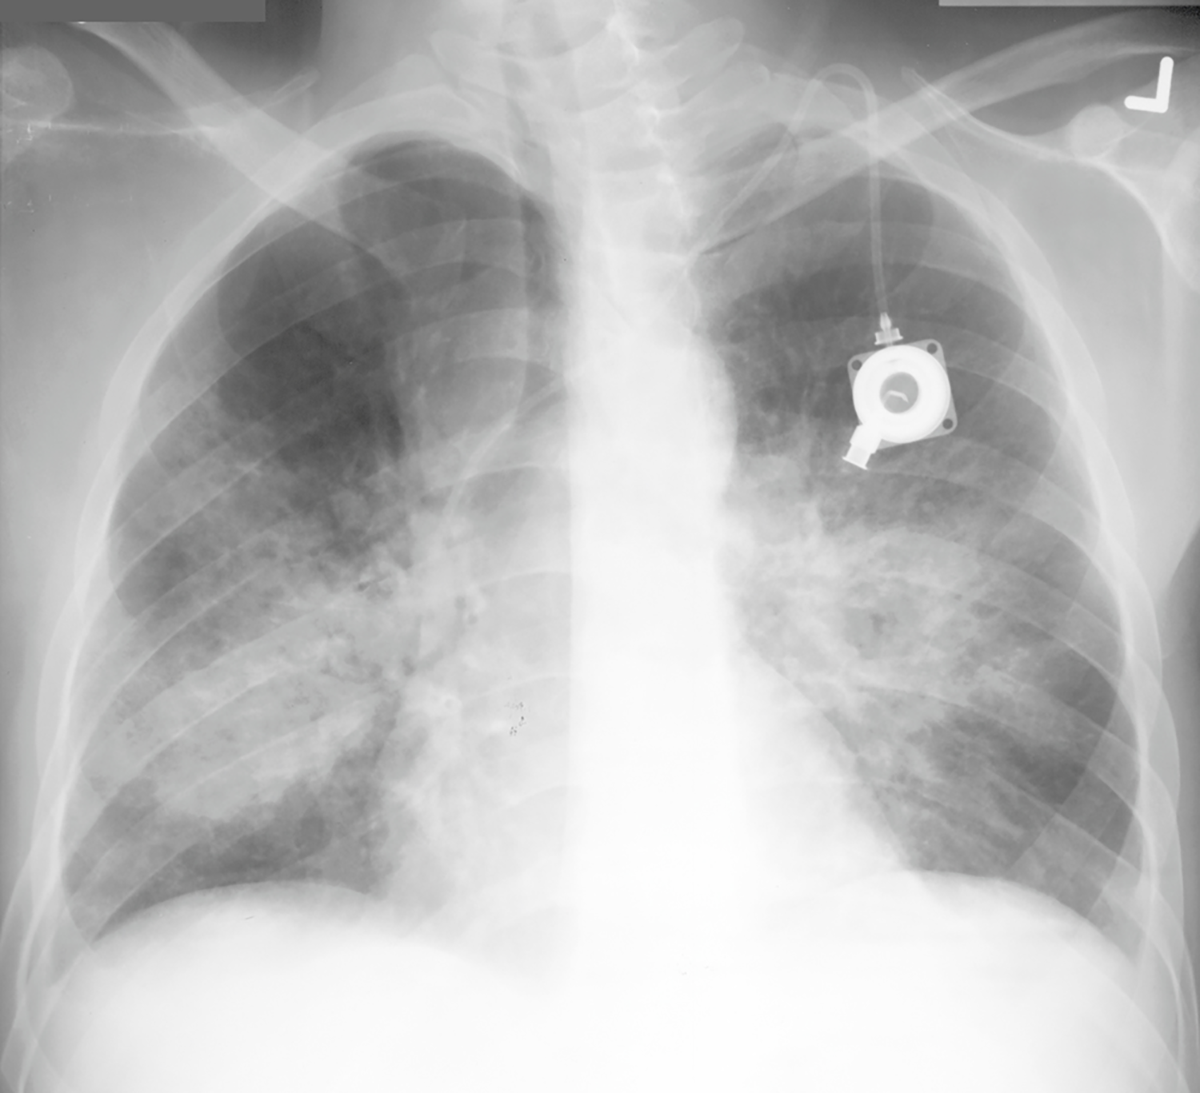

Topic 2

advanced case CHF

Further Explanation: